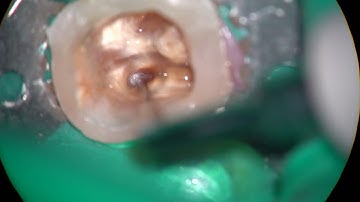

Removal of a non-visiblebroken file longer than 4 5mm from a curve more than 30 degrees